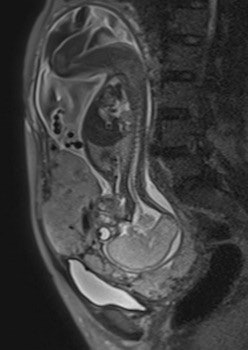

Their retrospective study included 25 pregnant women (mean age 35.16) -- 12 with histopathologically proven placental invasion and 13 without to act as a control -- who were investigated by prenatal MRI without IV contrast at three hospitals using three different 1.5-tesla MRI units (Magnetom Symphony, Siemens Healthcare; Intera, Philips Healthcare; Signa, GE Healthcare). The women underwent MR imaging between June 2007 and December 2009 after obstetrician referral for suspected placental invasion upon standard pregnancy ultrasound exams. The MRI protocols were similar and included T1-weighted volume interpolated gradient-echo MR sequences in the sagittal and axial plane, single-shot fast spin-echo T2-weighted MR sequences, and true fast imaging with steady-state precession in the axial, sagittal, and coronal planes.

Two senior radiologists with more than five years of practical experience in abdominal MRI and two junior radiologists with less than three years of abdominal MRI experience blindly and independently reviewed MR exams for six previously defined MR features described in the literature as useful for predicting placental invasion. The features included dark intraplacental bands on T2-weighted images, a focally interrupted myometrial border, heterogeneous intraplacental signal intensity, abnormal uterine bulging, "tenting" of the bladder, and infiltration of the adjacent pelvic organs.

In normal patients, the uterus presents as an inverted pear-shape organ. At MRI, the normal placenta appears as a soft-tissue structure, located along the uterine walls, with variable morphology and homogeneous, intermediate, signal intensity on T2-weighted images. In Alamo's study, T2-hypointense placental bands, a focally interrupted myometrial border, infiltration of the pelvic organs, and tenting of the bladder proved to be the best signs of predicting placental invasion.

"The combination of these four imaging features shows a stepwise multiple regression coefficient of 0.36. Our data suggest that this 'gold combination' increases the specificity of MRI and may enable a reliable detection of placental implantation disorders," they wrote.